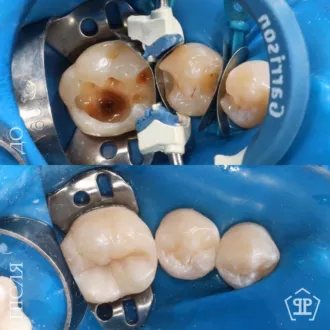

Пациент обратился с жалобами на повышенную чувствительность к воздуху и сладкую пищу в области угловых зубов. После обследования и диагностического разбора КТ был диагностирован глубокий контактный кариес 14 и 15 зуба. Произведено изолирование зубов кофердамом, с последующим раскрытием кариозных полостей и последующим восстановлением утраченных тканей методом художественной реставрации.